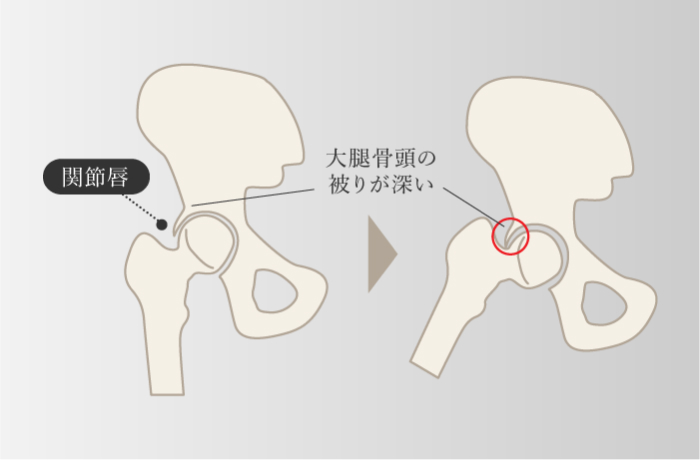

変形性股関節症

-

股関節に過剰な負担がかかり、軟骨がすり減ることで起こる。 股関節は、受け皿になる寛骨臼と、大腿骨頭がかみ合ってできている球関節で、この大腿骨頭が寛骨臼にしっかりと被さることで体重が支えられている。 大腿骨頭の被り方が先天的に浅い骨格の人は、体重のかかる面が少ないため、加齢とともに股関節に負担が集中し、軟骨のすり減る割合が通常よりも多くなる。